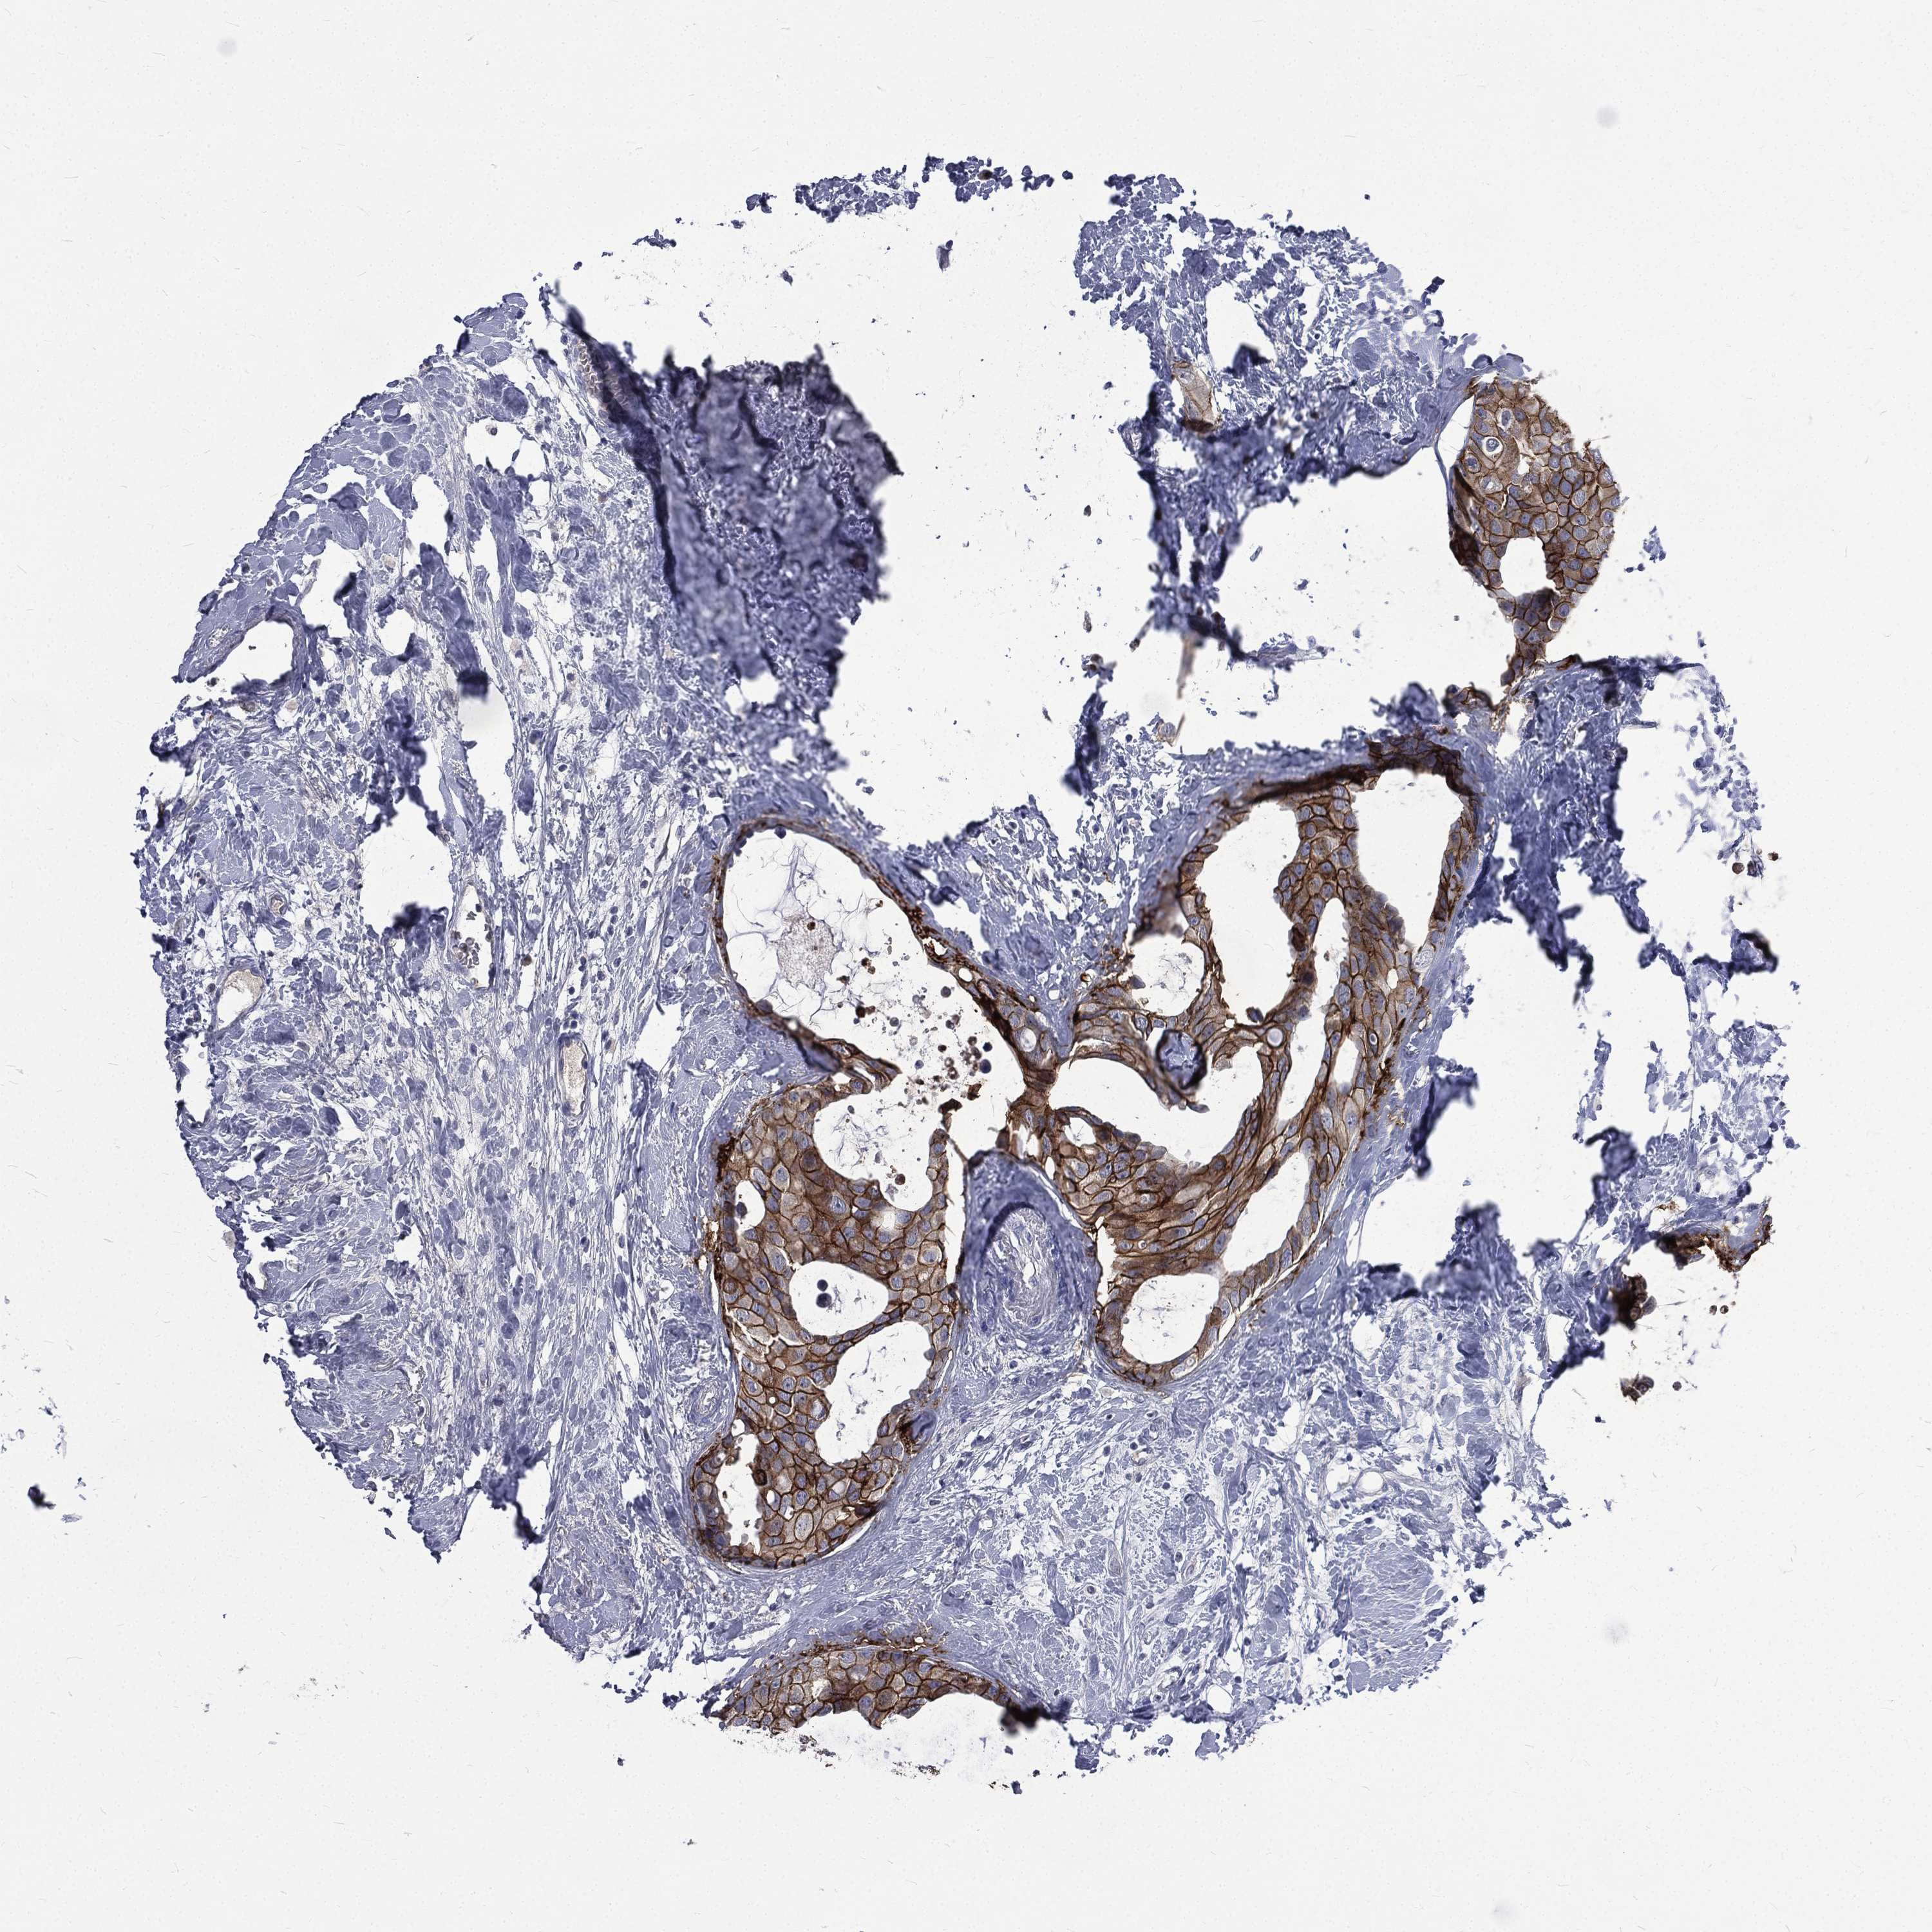

BRCA TCGA BRCA VALIDATION PROTEIN EXPRESSION

Breast cancer

Human cancer